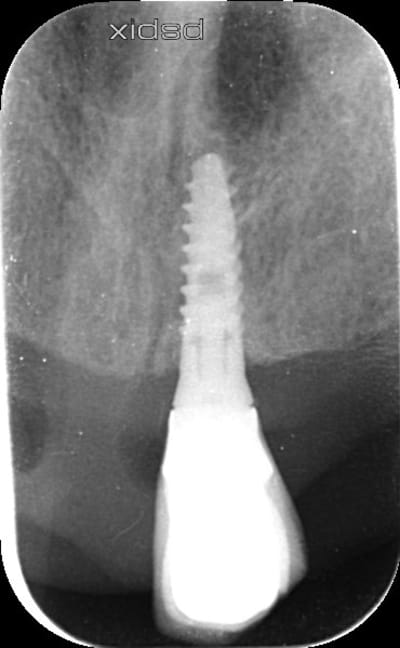

Bonjour, pourriez-vous m'indiquer la marque et le modèle de cet implant ?

Posé en France.

Merci

Quelqu'un aurait une idée ? Pluton par exemple, au hasard :-)

Ou sinon quelle est la méthode pour pouvoir identifier un implant ?